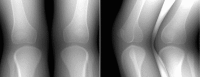

Purpose: Human subjects in standing positions are apt to show much more involuntary motion than in supine positions. The authors aimed to simulate a complicated realistic lower body movement using the four-dimensional (4D) digital extended cardiac-torso (XCAT) phantom. The authors also investigated fiducial marker-based motion compensation methods in two-dimensional (2D) and three-dimensional (3D) space. The level of involuntary movement-induced artifacts and image quality improvement were investigated after applying each method.

Methods: An optical tracking system with eight cameras and seven retroreflective markers enabled us to track involuntary motion of the lower body of nine healthy subjects holding a squat position at 60° of flexion. The XCAT-based knee model was developed using the 4D XCAT phantom and the optical tracking data acquired at 120 Hz. The authors divided the lower body in the XCAT into six parts and applied unique affine transforms to each so that the motion (6 degrees of freedom) could be synchronized with the optical markers' location at each time frame. The control points of the XCAT were tessellated into triangles and 248 projection images were created based on intersections of each ray and monochromatic absorption. The tracking data sets with the largest motion (Subject 2) and the smallest motion (Subject 5) among the nine data sets were used to animate the XCAT knee model. The authors defined eight skin control points well distributed around the knees as pseudo-fiducial markers which functioned as a reference in motion correction. Motion compensation was done in the following ways: (1) simple projection shifting in 2D, (2) deformable projection warping in 2D, and (3) rigid body warping in 3D. Graphics hardware accelerated filtered backprojection was implemented and combined with the three correction methods in order to speed up the simulation process. Correction fidelity was evaluated as a function of number of markers used (4-12) and marker distribution in three scenarios.

Results: Average optical-based translational motion for the nine subjects was 2.14 mm (± 0.69 mm) and 2.29 mm (± 0.63 mm) for the right and left knee, respectively. In the representative central slices of Subject 2, the authors observed 20.30%, 18.30%, and 22.02% improvements in the structural similarity (SSIM) index with 2D shifting, 2D warping, and 3D warping, respectively. The performance of 2D warping improved as the number of markers increased up to 12 while 2D shifting and 3D warping were insensitive to the number of markers used. The minimum required number of markers for 2D shifting, 2D warping, and 3D warping was 4-6, 12, and 8, respectively. An even distribution of markers over the entire field of view provided robust performance for all three correction methods.

Conclusions: The authors were able to simulate subject-specific realistic knee movement in weight-bearing positions. This study indicates that involuntary motion can seriously degrade the image quality. The proposed three methods were evaluated with the numerical knee model; 3D warping was shown to outperform the 2D methods. The methods are shown to significantly reduce motion artifacts if an appropriate marker setup is chosen.